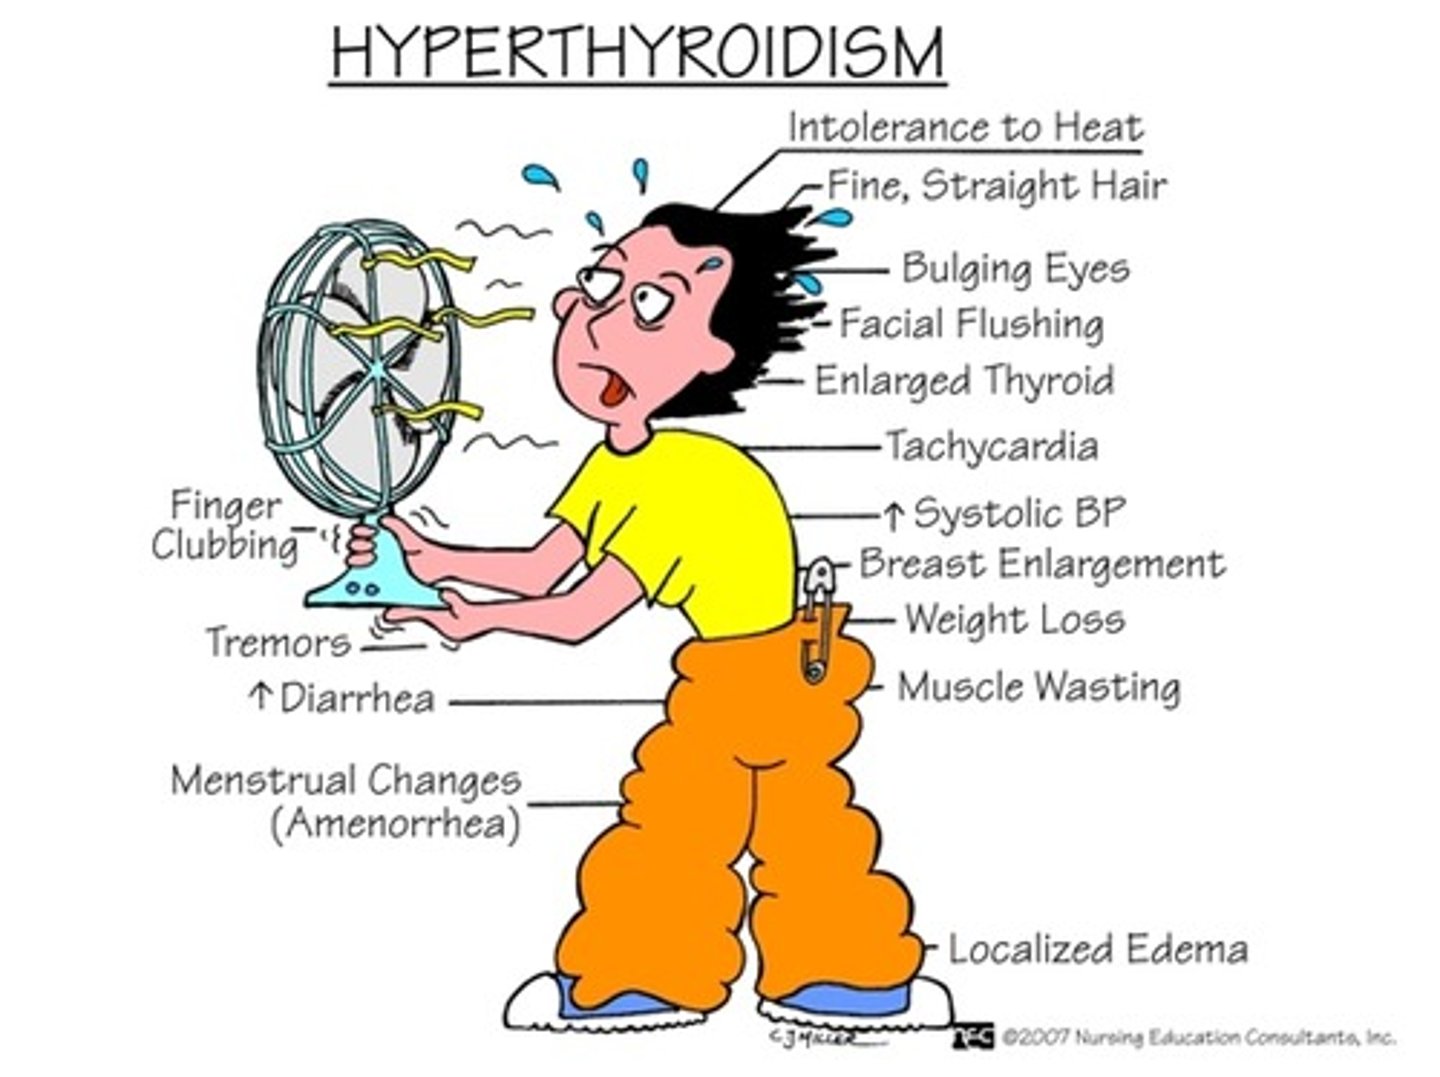

bulging eyes (exophthalmos), weight loss, and Graves disease are all due to _____

hyperthyroidism

signs/symtoms of skinny, weight loss

Graves disease